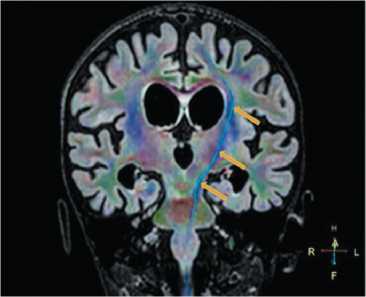

During the follow-up 6 months from injury, MEPs could not be reliably verified, although even a single stimulus of 50% intensity triggered a 25-sec generalized tonic seizure. Therefore, the number of stimuli was limited. CST reconstruction on follow-up MR tracto graphy demonstrated substantial volume predominance of the right CST originated from SMA and absence of CST from M1 (Fig. 2).

Video EEG monitoring was performed in external facility. Epileptiform discharges in the vertex region (Fz-Cz-Pz) with periodic spreading to the left central parietal region (C3-P3) or bilaterally were registered in wakefulness and sleep; the prevalence was average in sleep and low in wakefulness. During the recording period, 4 generalized motor tonic seizures accompanied by rhythm desynchronization and fast-wave beta-band activity (ictal pattern) and events of non-epileptologic genesis were recorded (Fig. 3). The child was consulted by an epileptologist, and depakine (8 mg QD, 33 mg/kg QD) and clonazepam (1.5 mg QD) were prescribed.

Fig. 3. EEG monitoring in patient S. during the awake stage in 6 months from injury.

Bipolar montage, paper speed 10 sec/page, sensitivity 7 µV/div, low-pass filter: 70 Hz, high-pass filter: 1 Hz. Ictal pattern (red arrow).